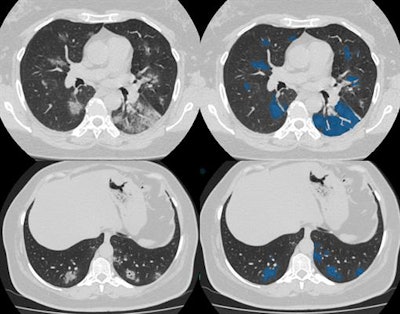

"The study from the scanner is transferred to URIS right away and processed by algorithms. Then a radiologist receives both the original image and the image processed by AI. The doctor opens a worklist of studies on his/her computer which need to be interpreted. Preliminary study markings of suspected pathology made by AI services are available to a specialist," he said.

"When a radiologist opens CT scan images, he/she sees a copy of the original image, on which AI has highlighted pathological findings in red. This is how the algorithm draws the doctor's attention to the lung areas with a probable lesion," he continued. "To help with interpretation, AI can generate a report where it indicates the probability of viral pneumonia."

The AI solution is capable of learning from the database containing the CT scans with marked-up annotated lung lesions, aggregated by the Moscow Center for Diagnostics and Telemedicine.The final conclusion, diagnosis, and further treatment, remain the sole responsibility of the doctor, he concluded.